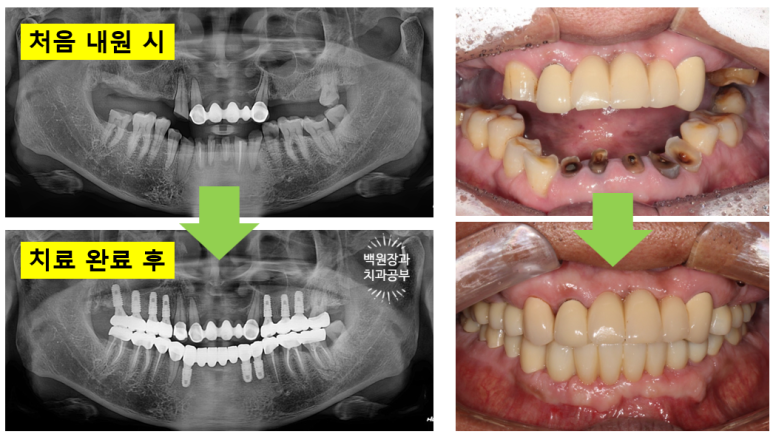

Before & After!!

한 장의 슬라이드로 요약해 보았습니다.!

위의 두 장의 사진이 저희 병원에 처음 내원하셨을 때의 사진입니다.

아래 두 장의 사진은 저희 병원에서 약 9개월간의 치료를 받으신 후의 결과이구요.

식사가 거의 불가했던 환자분이 어금니를 회복함으로 인해 양쪽으로 식사가 가능한 상태가 되셨고,

뿌리만 남아 기능적, 심미적으로 불량했던 아래 앞니는 임플란트 치료를 통해 올바른 길이와 모양으로 재탄생 하였습니다.